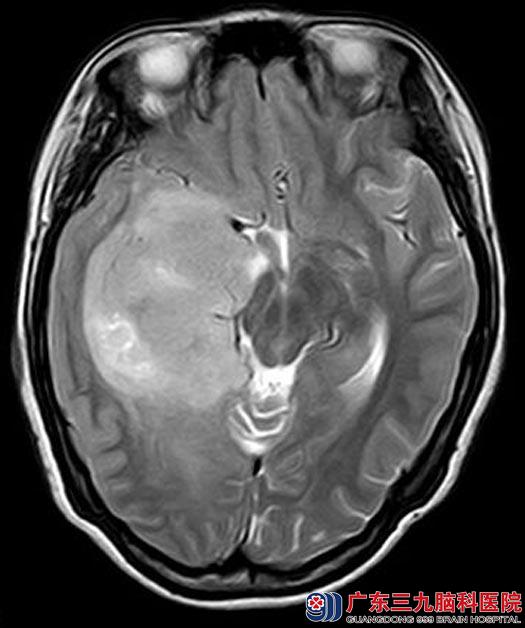

入住广东三九脑科医院综合神经外科,头颅MR检查提示:右侧颞岛叶巨大占位,增强后病灶局部示斑片状轻至中度强化,大部分未见强化;病变边界部分欠清,大小约为7.0cm×5.3cm×4.5cm,病变累及胼胝体压部。邻近外侧裂区血管明显受压移位,右侧脑室受压变形变窄,中线结构向左侧偏移,考虑弥漫性星形细胞瘤合并局部间变可能。